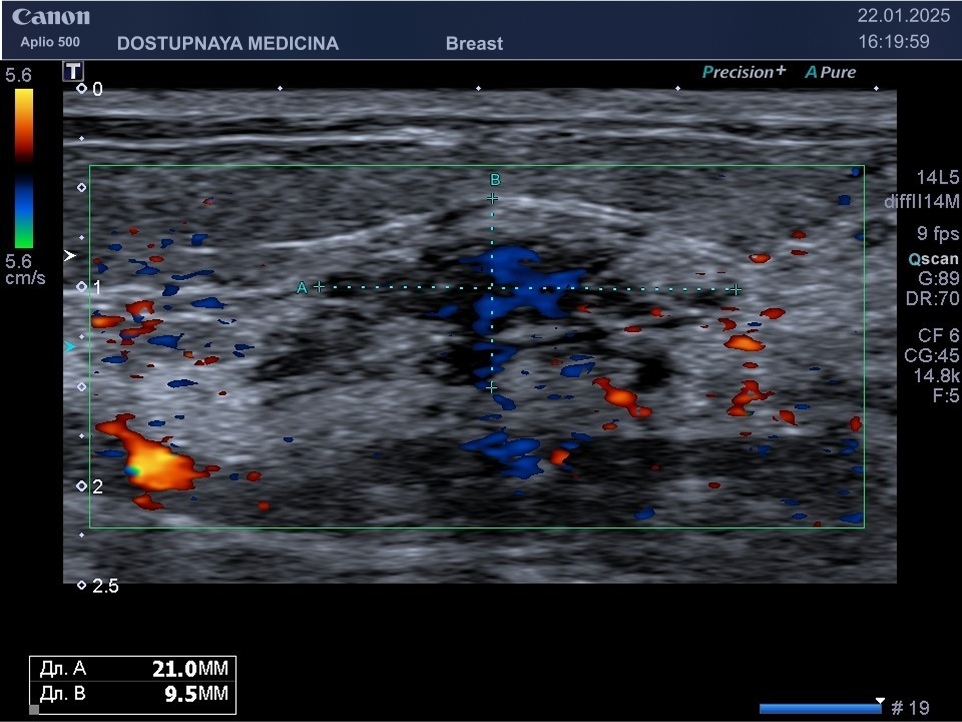

Кисты могут воспаляться, тогда при ультразвуковом исследовании в режиме ЦДК вокруг кисты отмечается усиление кровотока, пациентка при этом жалуется обычно на уплотнение и боль в области кисты молочной железы. Воспаление кисты может привести к её абсцедированию.

При ультразвуковом исследовании в кисте может быть визуализирован папиллярный компонент с кровотоком в режиме ЦДК. Так могут выглядеть цистаденопапилломы, которые считаются аблигатным предраком.